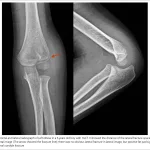

大腿骨頚部が消失して, 骨折部がズレて短縮しています.

骨折してから3週間以上経過してから紹介されて受診された超高齢患者さんでした.

骨折部が短縮しており, 大腿骨頚部が溶けてなくなっており, やや難渋しました.